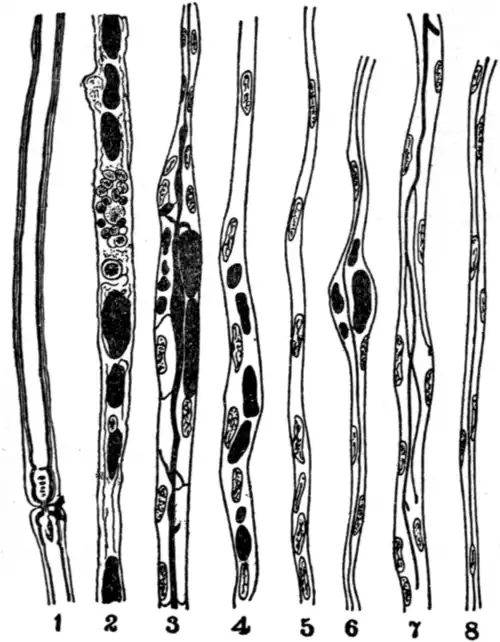

![]() | |

| Fig. 17.—Diagram to illustrate various stages in degeneration and regeneration of medullated nerve fibres. | |

| 1, | Normal medullated nerve with node of Ranvier. |

| 2, | Degenerated nerve, ten days after section, showing degenerated myelin stained black; disappearance of axis-cylinder. |

| 3, | Central end of cut nerve, showing at the top an axis-cylinder budding out, proliferated neurilemmal cells, and still some degenerated myelin in sheath. |

| 4, | Peripheral cut end of same, showing proliferated neurilemmal cells, still some degenerated myelin. |

| 5, | Complete absorption of degenerated myelin, proto-plasmic basis of new fibre formed out of neurilemmal cells. |

| 6, | A new fibre, with axis-cylinder. |

| 7, | Central end of cut nerve at junction, showing an axis-cylinder sprouting and forming a number of axis-cylinder processes, which grow into the peripheral end to form new channels of conduction. |

| 8, | Is a new regenerated fibre resembling a sympathetic fibre in having as yet no myelin sheath; as the nerve becomes excitable and stimulus passes, a myelin sheath is formed. |

its function. Fig. 17, Nos. 1-8, with explanatory text, shows